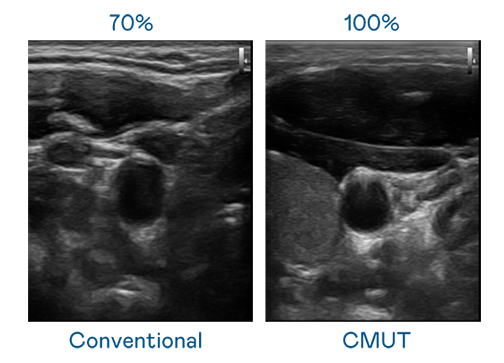

CMUT 技术是一种用电容式微机电元件来产生超音波讯号的技术。与传统 PZT 压电式技术相比,CMUT 频宽增加 30%,更宽频的超音波讯号让影像解析度大幅提升,是实现高影像品质医疗超音波扫描、促进精准医疗发展的关键技术。

大频宽带来超清晰影像

超音波影像的解析度高低,首先取决于探头能发出的讯号频宽。17com黑料爆料视频在线看免费版 CMUT 可提供高清晰的超音波讯号,提供高频宽、高灵敏度、影像纹理细节更高的超音波影像,协助医护人员缩短影像判读时间及利用精准的医疗影像进行诊断。